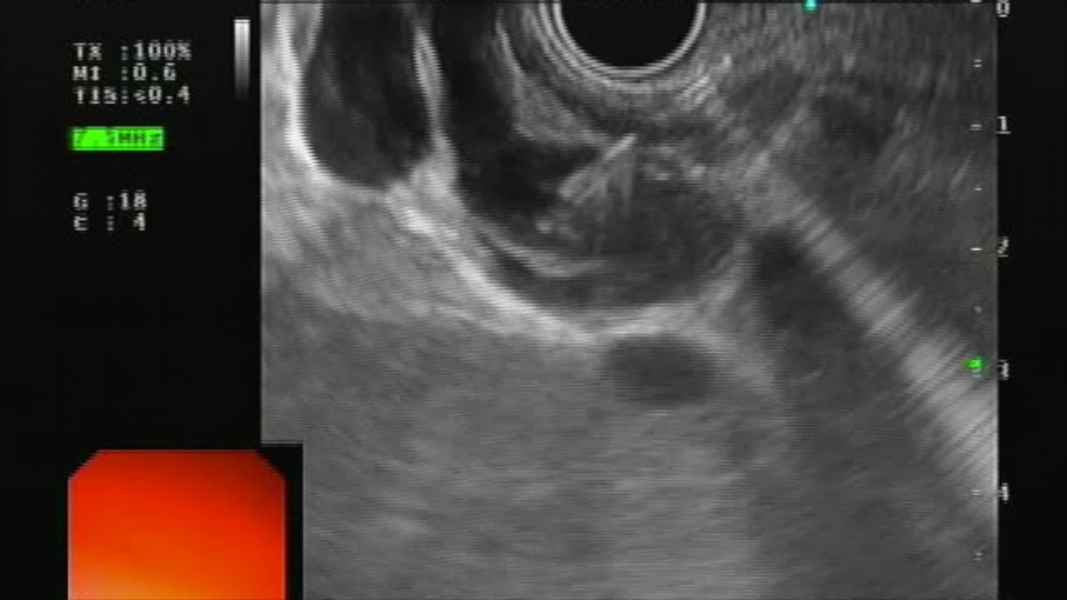

Through the needle wall biopsy in pancreatic cystic lesions

Vídeo